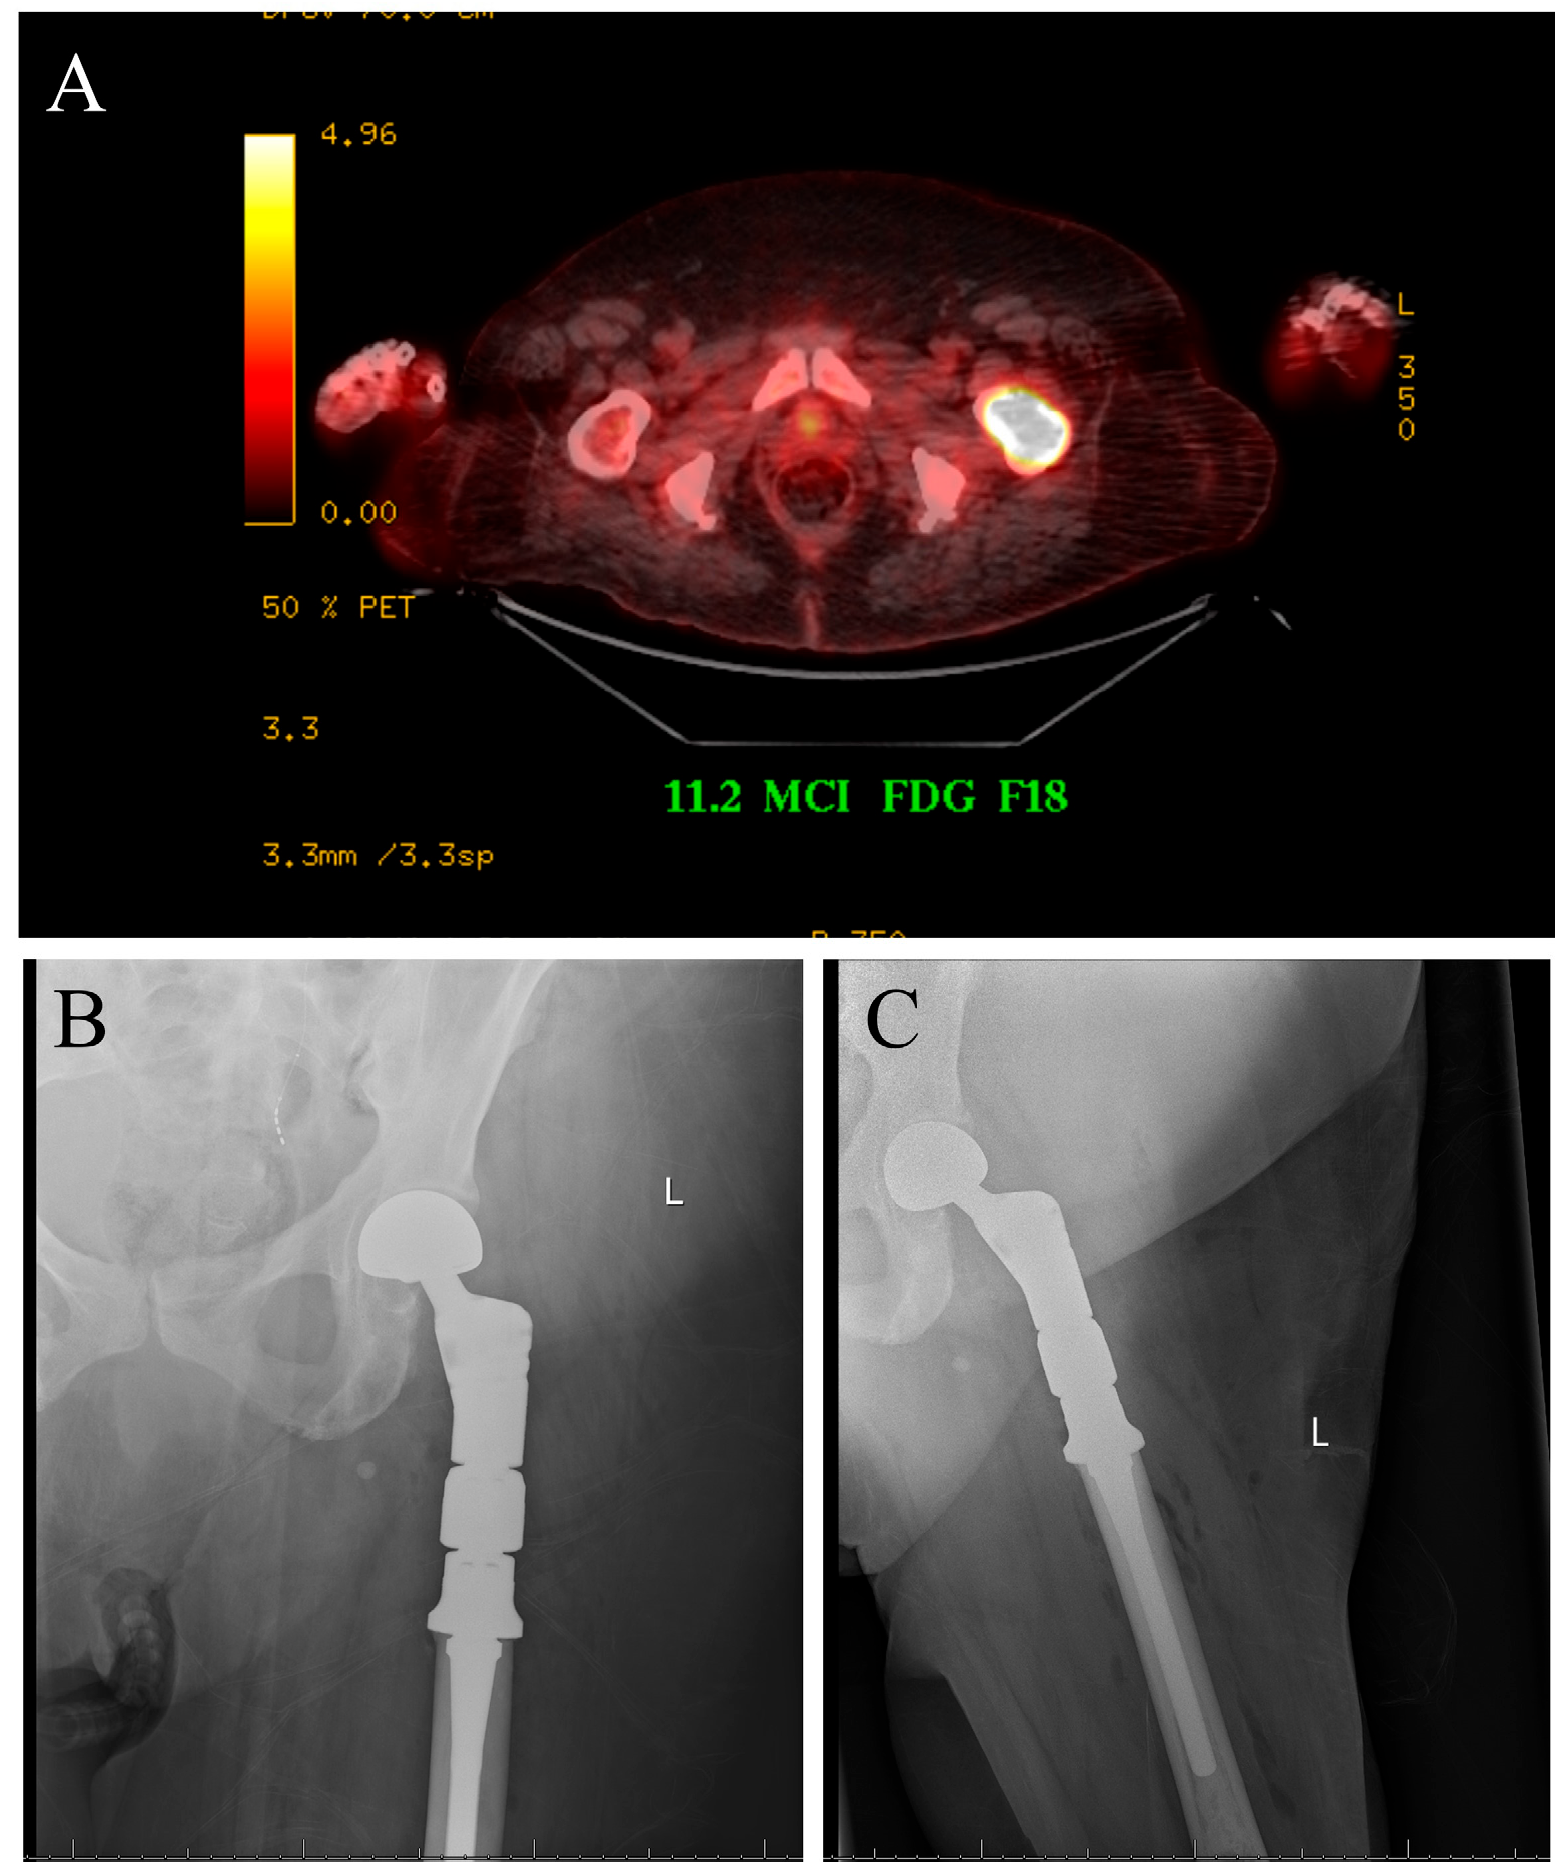

The case displayed in Figure 1 illustrates the surgical management of a solitary bone lesion on the hip by the senior author of this article.

Figure 1.

Seventy-five-year-old female with newly diagnosed breast cancer and pain with weight-bearing on the left hip. (A) Axial cut PET-CT showing solitary bone lesion biopsy proven breast cancer. (B,C) Patient underwent resection of left proximal femur and reconstruction with proximal femur megaprosthesis.